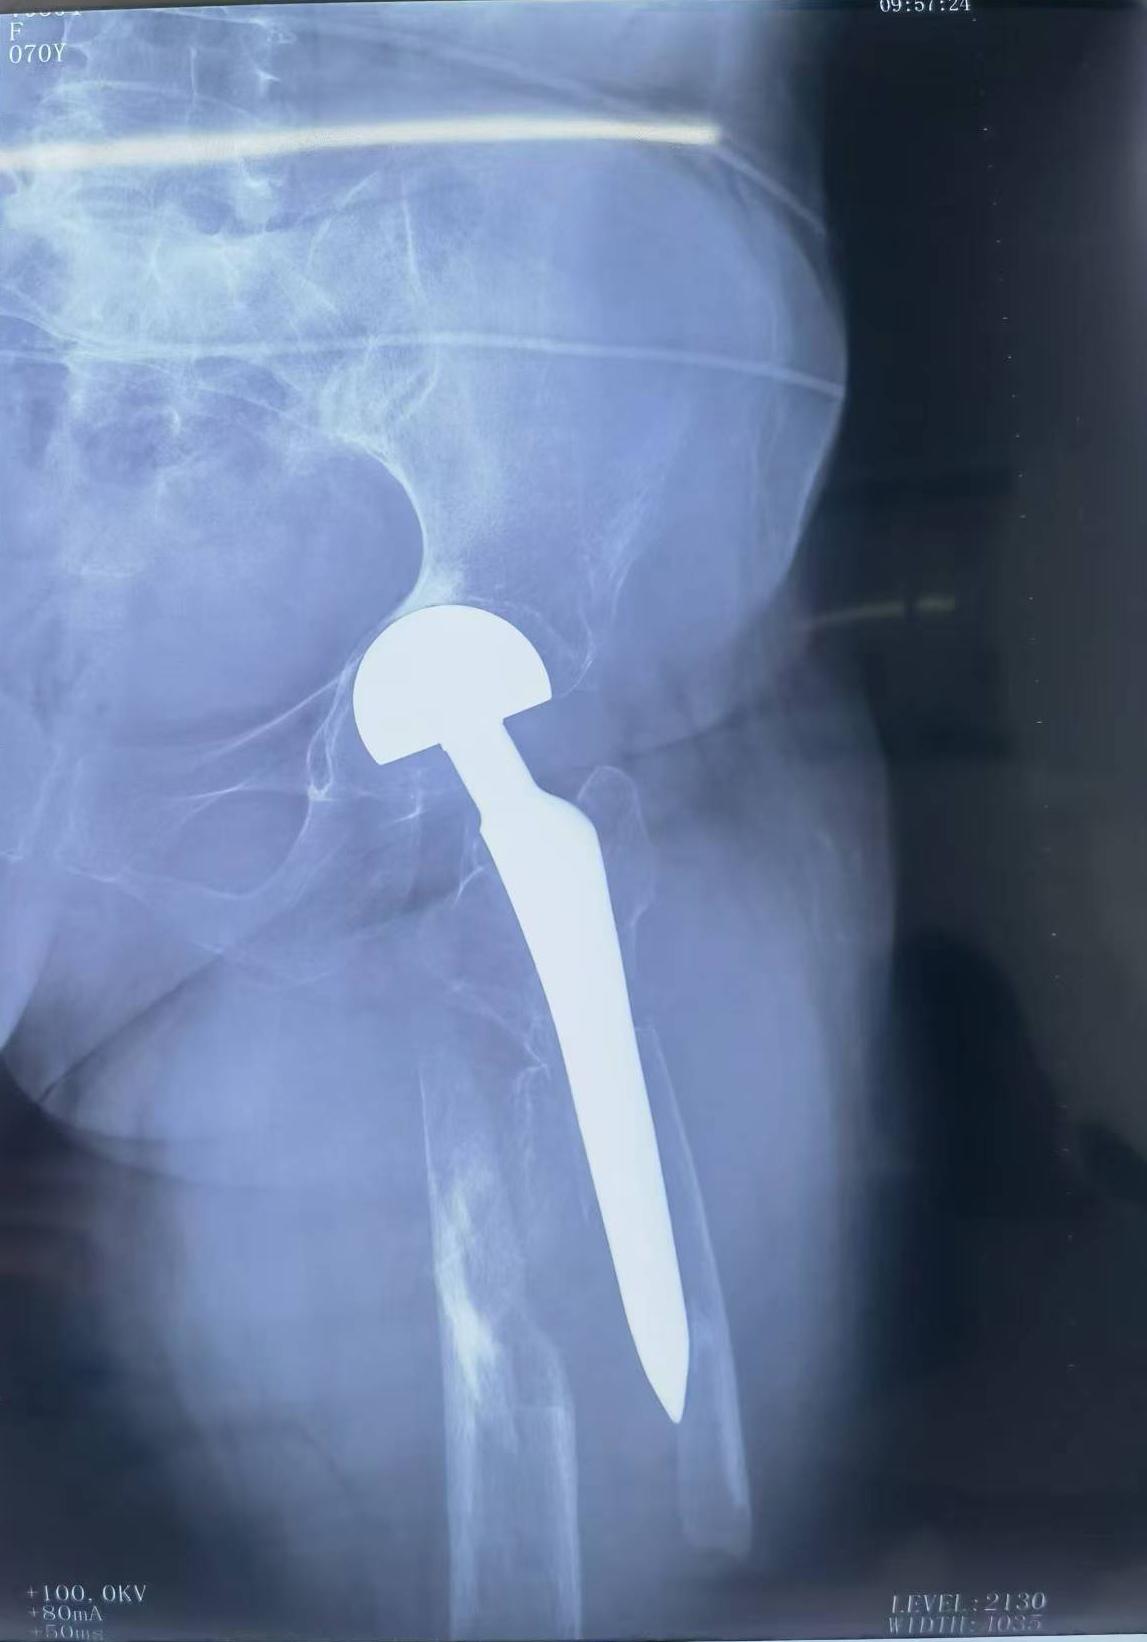

假体周围骨折。髋关节置换术后假体周围骨折,再次翻修,关注老年患者骨质疏松问题,降低骨折发生率。